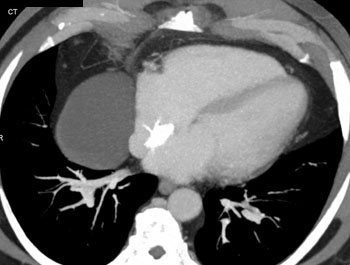

Question 5: 47 year old male with mass discovered on CT during chest pain workup. What is the diagnosis?

Diagnosis: Pericardial cyst

• Usually at right anterior costophrenic angle

• Water density on CT

• 2-30 cm in size

• Homogeneous without any enhancement

• Anomalous outpouching of the parietal pericardium

• Right costophrenic location in 70-90% of cases

Pericardial Cysts: CT Findings

• Smoothly marginated lesion surface

• Less than 10 HU

• No enhancement on contrast studies

• Size range from 2-30 cm